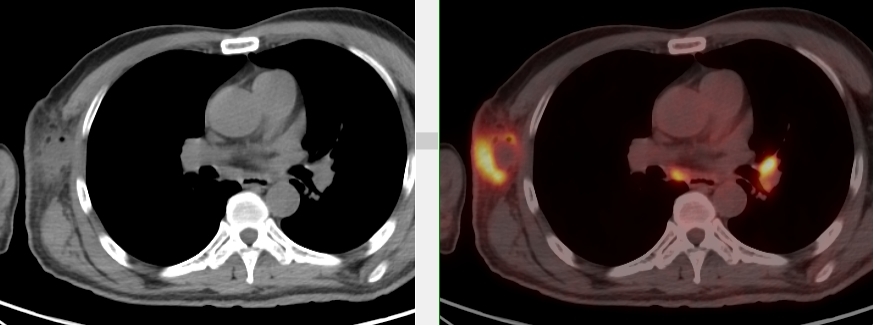

頸胸部多處代謝異常病灶

完善胸部強化CT考慮縱隔MT并縱隔、右腋窩及雙肺門多發(fā)腫大淋巴結,后行超聲引導下行右腋窩腫物穿刺活檢術,病理首先考慮惡性腫瘤,因穿刺組織局限,腫瘤細胞成分過少,不能明確診斷。

完善PET/CT檢查示:右側腋窩、雙側中下頸部、縱隔、雙側肺門多發(fā)MT,建議淋巴結活檢。后患者行右腋窩淋巴結切除活檢術,經北京大學第三醫(yī)院病理科會診示:右腋窩淋巴結惡性腫瘤,呈淋巴竇內生長模式,瘤細胞呈上皮樣,異型性明顯,伴中性粒細胞浸潤。結合病史及免疫組化,考慮為SMARCA4(BRG1)缺失的胸部腫瘤,伴神經內分泌標記表達。

胸部SMARCA4缺失腫瘤好發(fā)部位為縱隔、肺、胸膜,多呈侵襲性生長,普遍發(fā)生轉移,累及骨、肺、腦、腎上腺等,預后較差。

本例為罕見病理類型的腫瘤,影像學表現無明顯特異性,診斷困難。強化CT和穿刺病理已基本明確為惡性腫瘤,行PET/CT檢查一是為了全身檢查,完善分期,二是根據PET代謝情況指導進行生物靶區(qū)活檢,進一步明確病理診斷。最終,PET/CT除縱隔病變外發(fā)現更多頸胸部淋巴結代謝異常,綜合考慮后對腋窩淋巴結進行切除活檢,最終得到病理證實。